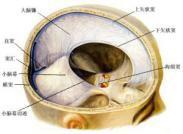

急性硬脑膜下血肿

628健康网为您分享有关急性硬脑膜下血肿的症状,急性硬脑膜下血肿的治疗方法,急性硬脑膜下血肿的预防知识,急性硬脑膜下血...

慢性硬脑膜下血肿

628健康网为您分享有关慢性硬脑膜下血肿的症状,慢性硬脑膜下血肿的治疗方法,慢性硬脑膜下血肿的预防知识,慢性硬脑膜下血...

颅后窝血肿

628健康网为您分享有关颅后窝血肿的症状,颅后窝血肿的治疗方法,颅后窝血肿的预防知识,颅后窝血肿的症状图片,颅后窝血肿...

急性脑内血肿

628健康网为您分享有关急性脑内血肿的症状,急性脑内血肿的治疗方法,急性脑内血肿的预防知识,急性脑内血肿的症状图片,急...